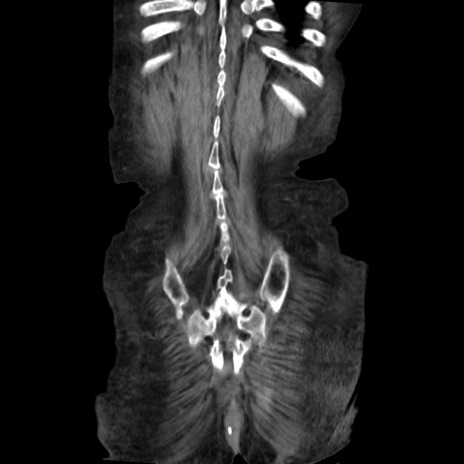

症例31(冠状断像)

症例

【症例】80歳代 女性

【主訴】腹部膨満感

【現病歴】他院にて肝硬変にてフォロー中。1週間前から便秘、腹部膨満感、臍部腫瘤あり受診となる。

【既往歴】肝硬変

【身体所見】腹部膨隆あり、皮膚変化なし、疼痛なし。

【データ】WBC 4600、CRP 0.25